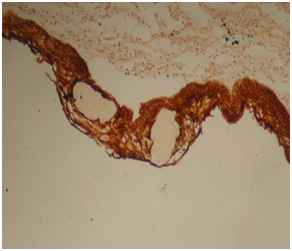

Craniopharyngioma are histologically a benign neoplasm that occurs in the sellar and suprasellar region, with an infiltrative growth pattern, accounts for 1.2-4.6% of all intracranial tumors.1 They are the most common non-neuroepithelial intracerebral neoplasm in children accounting for 5-10% of intracranial tumors in this age group. A bimodal age distribution of ACP is observed, with peaks in children aged 5-15years and adults 45-60years.1 They are often difficult to excise surgically, and they have a 10% to 40% recurrence rate.2 There are at two types of craniopharyngioma: Adamantinomatous craniopharyngioma (ACP) and papillary craniopharyngioma (PCP). Both have distinct morphology and different clinical behavior. ACP has at least four different squamous histological areas: superficial mature squamous (SMS), loosely cohesive aggregates of squamous cells known as “stellate reticulum” (SR), palisaded basal columnar (PBC) cells and nodules of wet keratin (WK) (Figure 1, Figure 2 & Figure 3). Cystic cavities containing squamous debris are lined by flattened epithelium. PCP occurs virtually exclusively in adults with mean age of 40-50years.3,4 Histologically, it is different from ACP by lacking nuclear palisading, wet keratin, and dystrophic calcification.5

Figure 1 Cystic spaces within squamous cells.